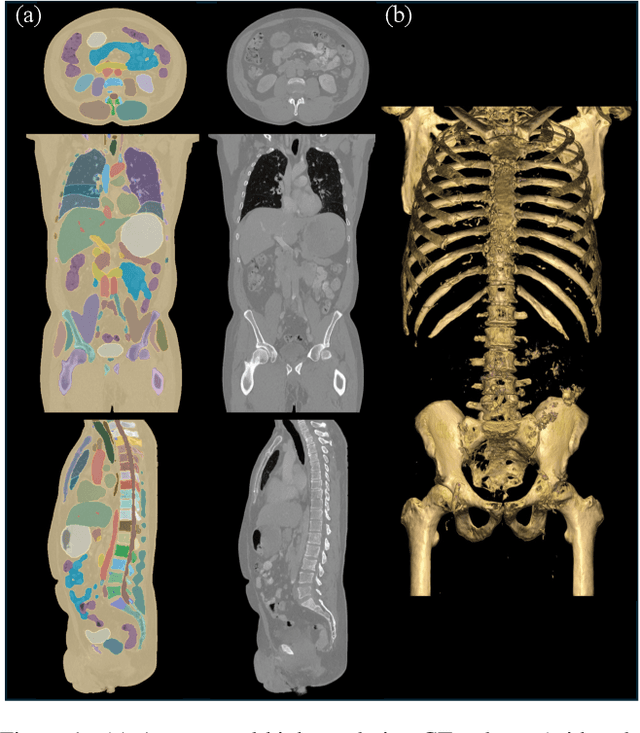

Abstract:Recent progress in vision-language modeling for 3D medical imaging has been fueled by large-scale computed tomography (CT) corpora with paired free-text reports, stronger architectures, and powerful pretrained models. This has enabled applications such as automated report generation and text-conditioned 3D image synthesis. Yet, current approaches struggle with high-resolution, long-sequence volumes: contrastive pretraining often yields vision encoders that are misaligned with clinical language, and slice-wise tokenization blurs fine anatomy, reducing diagnostic performance on downstream tasks. We introduce BTB3D (Better Tokens for Better 3D), a causal convolutional encoder-decoder that unifies 2D and 3D training and inference while producing compact, frequency-aware volumetric tokens. A three-stage training curriculum enables (i) local reconstruction, (ii) overlapping-window tiling, and (iii) long-context decoder refinement, during which the model learns from short slice excerpts yet generalizes to scans exceeding 300 slices without additional memory overhead. BTB3D sets a new state-of-the-art on two key tasks: it improves BLEU scores and increases clinical F1 by 40% over CT2Rep, CT-CHAT, and Merlin for report generation; and it reduces FID by 75% and halves FVD compared to GenerateCT and MedSyn for text-to-CT synthesis, producing anatomically consistent 512*512*241 volumes. These results confirm that precise three-dimensional tokenization, rather than larger language backbones alone, is essential for scalable vision-language modeling in 3D medical imaging. The codebase is available at: https://github.com/ibrahimethemhamamci/BTB3D

Abstract:Generating 3D CT volumes from descriptive free-text inputs presents a transformative opportunity in diagnostics and research. In this paper, we introduce Text2CT, a novel approach for synthesizing 3D CT volumes from textual descriptions using the diffusion model. Unlike previous methods that rely on fixed-format text input, Text2CT employs a novel prompt formulation that enables generation from diverse, free-text descriptions. The proposed framework encodes medical text into latent representations and decodes them into high-resolution 3D CT scans, effectively bridging the gap between semantic text inputs and detailed volumetric representations in a unified 3D framework. Our method demonstrates superior performance in preserving anatomical fidelity and capturing intricate structures as described in the input text. Extensive evaluations show that our approach achieves state-of-the-art results, offering promising potential applications in diagnostics, and data augmentation.

Abstract:Medical imaging analysis faces challenges such as data scarcity, high annotation costs, and privacy concerns. This paper introduces the Medical AI for Synthetic Imaging (MAISI), an innovative approach using the diffusion model to generate synthetic 3D computed tomography (CT) images to address those challenges. MAISI leverages the foundation volume compression network and the latent diffusion model to produce high-resolution CT images (up to a landmark volume dimension of 512 x 512 x 768 ) with flexible volume dimensions and voxel spacing. By incorporating ControlNet, MAISI can process organ segmentation, including 127 anatomical structures, as additional conditions and enables the generation of accurately annotated synthetic images that can be used for various downstream tasks. Our experiment results show that MAISI's capabilities in generating realistic, anatomically accurate images for diverse regions and conditions reveal its promising potential to mitigate challenges using synthetic data.